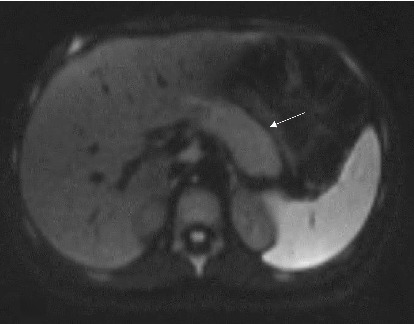

Abstract Image